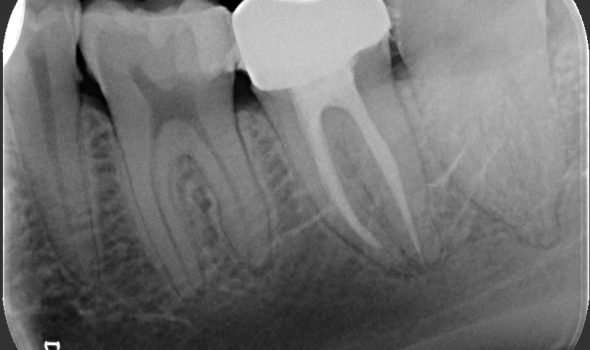

Una carie in stato avanzato può causare l’insorgenza di sintomatologia dolorosa. E’ questo il segnale del coinvolgimento della polpa dentaria dove risiedono nervi e vasi sanguigni, responsabili del dolore e attraverso il quale i batteri possono diffondere attraverso le radici e l’osso circostante. In questo caso è necessaria la devitalizzazione del dente tramite un trattamento endodontico volto a rimuovere i batteri dall’interno del dente ed otturare le radici. Questo trattamento permette di salvare il dente e poterlo protesizzare per ripristinarne la funzione.